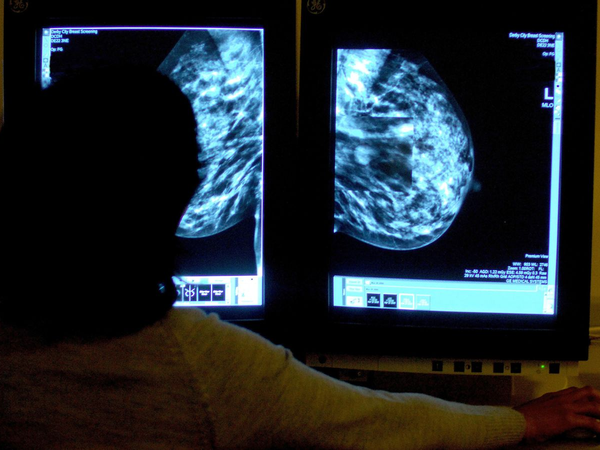

Στην τρίτη φάση της δοκιμής συμμετείχαν πάνω από 3.000 ασθενείς από 23 χώρες, με τους γιατρούς να χρησιμοποιούν εξετάσεις αίματος για την ανίχνευση μεταλλάξεων στο DNA των όγκων, ώστε να εντοπίζουν εγκαίρως σημάδια ανθεκτικότητας στις υπάρχουσες θεραπείες.

Ένα από τα πιο σημαντικά ευρήματα της μελέτης είναι η χρήση της λεγόμενης υγρής βιοψίας, δηλαδή η ανάλυση καρκινικού DNA (ctDNA) που κυκλοφορεί στο αίμα, για να εντοπιστεί εγκαίρως η ανθεκτικότητα του όγκου στη θεραπεία.

Η Δρ Κάθριν Έλιοτ από το Cancer Research UK χαρακτήρισε την εξέλιξη ως «ένα σαφές παράδειγμα του πώς οι αιματολογικές εξετάσεις αρχίζουν να μεταμορφώνουν τη θεραπεία του καρκίνου».

«Με την παρακολούθηση ελάχιστων ιχνών DNA του όγκου στο αίμα, οι ερευνητές μπόρεσαν να εντοπίσουν έγκαιρα σημάδια αντίστασης και να αλλάξουν θεραπεία πριν ο καρκίνος προλάβει να εξελιχθεί», ανέφερε χαρακτηριστικά.

Η τεχνική αυτή ενισχύει τη δυναμική της εξατομικευμένης ιατρικής και ενδέχεται να καθιερωθεί στο μέλλον ως βασικό εργαλείο στην παρακολούθηση ασθενών με προχωρημένο καρκίνο του μαστού.